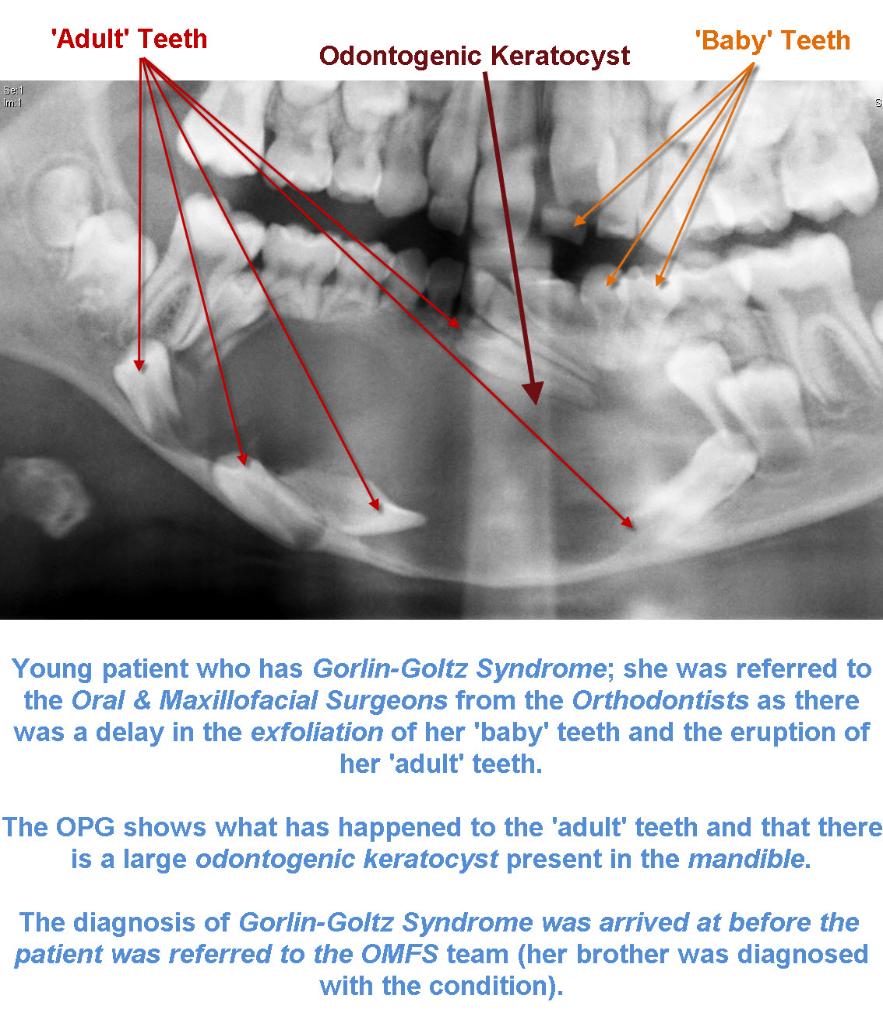

Treatment Of The Keratocystic Odontogenic Tumor Kcot In Patients With Gorlin Goltz Syndrome A Review Of The Literature With A Case Report Italian Journal Of Dental Medicine